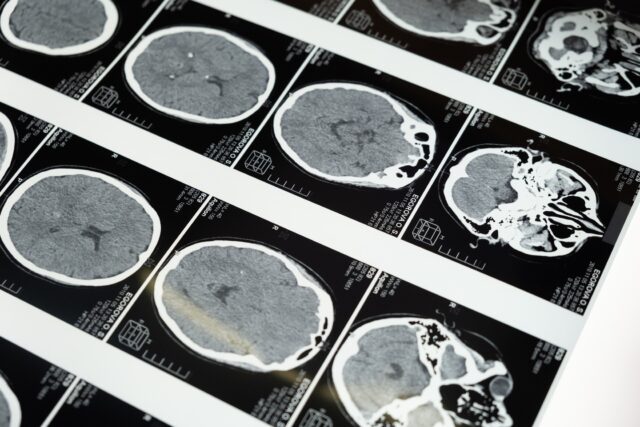

Εργαλείο τεχνητής νοημοσύνης αποκωδικοποιεί το γονιδίωμα του καρκίνου του εγκεφάλου κατά τη διάρκεια της χειρουργικής επέμβασης για την αφαίρεσή του. Η δημιουργία του προφίλ του όγκου σε πραγματικό χρόνο μπορεί να καθοδηγήσει τις χειρουργικές θεραπευτικές αποφάσεις. Η έρευνα δημοσιεύτηκε στο περιοδικό Med.

Η επιστημονική ομάδα, με επικεφαλής την Ιατρική Σχολή του Χάρβαρντ, σχεδίασε ένα εργαλείο τεχνητής νοημοσύνης που μπορεί να αποκωδικοποιήσει γρήγορα κατά τη διάρκεια χειρουργικής επέμβασης το DNA ενός όγκου στον εγκέφαλο, προκειμένου να προσδιορίσει τη μοριακή του ταυτότητα. Οι πληροφορίες αυτές είναι κρίσιμες, καθώς με την τρέχουσα προσέγγιση μπορεί να χρειαστούν από μερικές ημέρες έως και μερικές εβδομάδες για να συλλεχθούν.

Η γνώση του μοριακού τύπου ενός όγκου επιτρέπει στους νευροχειρούργους να λαμβάνουν αποφάσεις, όπως πόση ποσότητα εγκεφαλικού ιστού θα αφαιρεθεί και εάν θα χορηγηθούν αντικαρκινικά φάρμακα απευθείας στον εγκέφαλο την ώρα του χειρουργείου. Πέρα από τις αποφάσεις που λαμβάνονται κατά τη διάρκεια της χειρουργικής επέμβασης, η γνώση του μοριακού τύπου ενός όγκου παρέχει ενδείξεις σχετικά με την επιθετικότητα, τη συμπεριφορά και την πιθανή ανταπόκρισή του στις διάφορες θεραπείες.

Το εργαλείο ονομάζεται CHARM (Cryosection Histopathology Assessment and Review Machine) και αναπτύχθηκε χρησιμοποιώντας 2.334 δείγματα όγκων εγκεφάλου από 1.524 άτομα με γλοίωμα. Όταν δοκιμάστηκε, διέκρινε όγκους με συγκεκριμένες μοριακές μεταλλάξεις με ακρίβεια 93% και ταξινόμησε επιτυχώς τρεις κύριους τύπους γλοιωμάτων με διακριτά μοριακά χαρακτηριστικά. Επίσης, κατέγραψε με επιτυχία τα οπτικά χαρακτηριστικά του ιστού που περιβάλλει τα κακοήθη κύτταρα και εντόπισε κλινικά σημαντικές μοριακές μεταβολές σε έναν υπότυπο γλοιώματος που είναι λιγότερο επιθετικός και επομένως λιγότερο πιθανό να εισβάλει στον περιβάλλοντα ιστό. Τέλος, συνέδεσε την εμφάνιση των κυττάρων με το μοριακό προφίλ του όγκου και αυτό σημαίνει ότι ο αλγόριθμος μπορεί να εντοπίσει με ακρίβεια πώς η εμφάνιση ενός κυττάρου σχετίζεται με τον μοριακό τύπο ενός όγκου.